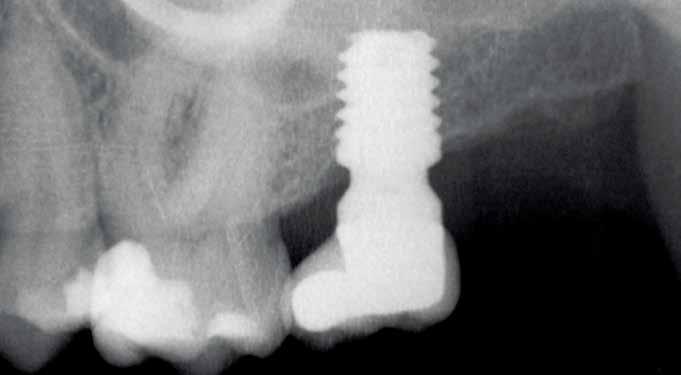

a positioner were used to establish bone loss. At each of the visits, periapical radiographs are taken with a parallelisation device to estimate the crestal bone loss. Marginal bone loss was measured on the last periapical radiograph taken with a follow-up positioner. Once the X-ray was obtained in digital format, it was calibrated using specific software (Digora for Windows, SOREDEX Digital Imaging systems) through a known length in the X-ray, such as the dental implant. Once the calibration measurement has been entered, the software performs a calculation based on this measurement to eliminate the magnification, allowing linear measurements to be made free of this error. The crestal bone loss was measured at two points: mesial and distal to each implant.

None of the implants failed during the follow-up period, resulting in 100% survival and no adverse surgical or prosthetic events were recorded. Images 1-7 show one of the cases included in the study.

Figure 3. Post-surgical panoramic X-ray with the recently placed implant.

Figure 4. Placement of the unitary transepithelial after the second phase at 5 months for progressive loading of the implant.

Figures 5-6 Clinical images of the patient at the time of crown placement. Figure 7. Radiographic image at 4 years of follow-up showing the bone stability of the implant and the rehabilitation.